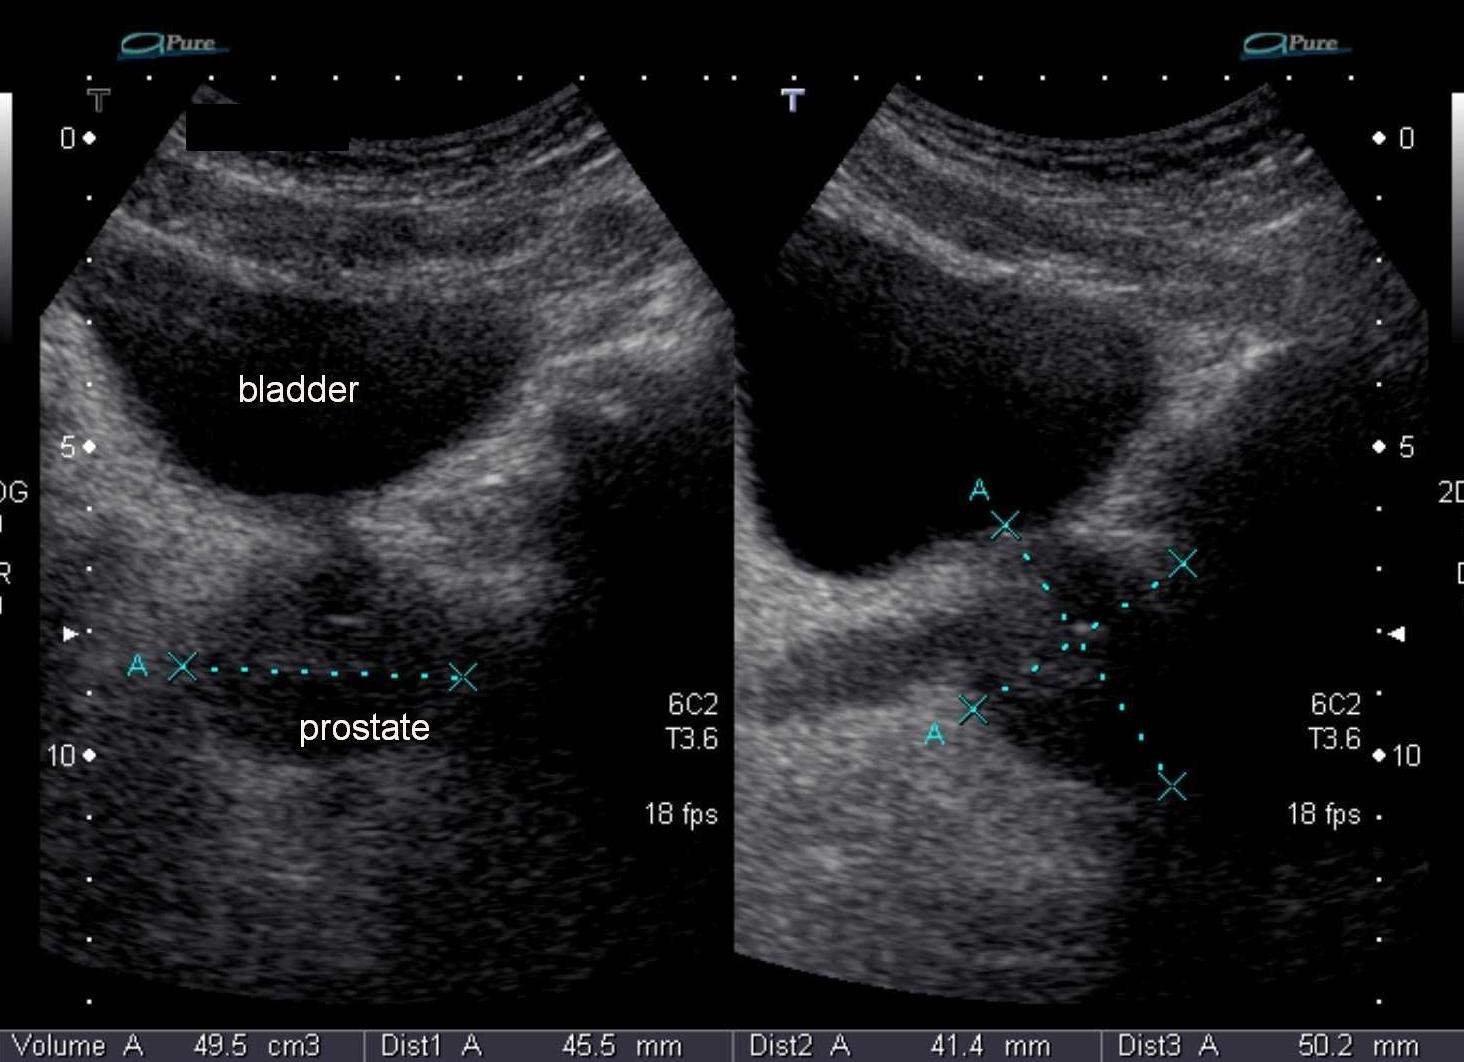

Данный метод позволяет оценить размеры простаты, ее объем и массу. Контуры органа должны быть четкими и ровными, не иметь нарастаний и выпуклостей. Далее пациент должен будет помочиться, чтобы врач смог измерить уровень остаточной мочи, что является важной характеристикой для некоторых заболеваний.

Трансабдоминальное УЗИ предстательной железы (ТАУЗИ) – диагностическое мероприятие, которое проводится для выявления нарушений в области простаты. Процедура широко используется для выявления структуры размеров и контура внутренних репродуктивных органов. Сканирование осуществляется через брюшную полость. Для увеличения информативности пациенту следует предварительно выпить 1,5 л воды, чтобы наполнить мочевой пузырь.

3. Датчик располагается под углом в 30 градусов в той области, где находится мочевой пузырь и простата. Диагностика проводится в поперечной и продольной плоскости.

Нормы предстательной железы:

• размеры – длина (от 24 до 40 мм), толщина (от 15 до 25 мм), ширина (от 30 до 45 мм);

• эхо-плотность однородная, без очаговых участков понижения или повышения сигнала;

• семенные пузырьки (диаметр – 1 см) — визуализируются в качестве удлиненных анэхогенных образований;

• форма – треугольная или полукруглая;

• границы – четкие и явные.

Объем простаты варьируется в зависимости от возраста пациента. Нормальные показатели высчитываются по формуле: V= 0,13 х возраст + 16,4.

Объем мочи после опорожнения мочевого пузыря должен быть не более 15 мл. В противном случае речь идет о патологии. Если специалист определяет увеличение размеров простаты, то возможен простатит или доброкачественная опухоль. Наличие явных комков ткани указывают на злокачественные образования. Рак может быть определен в качестве нерегулярных структур в области железы, искажающих нормальные эхо-сигналы.